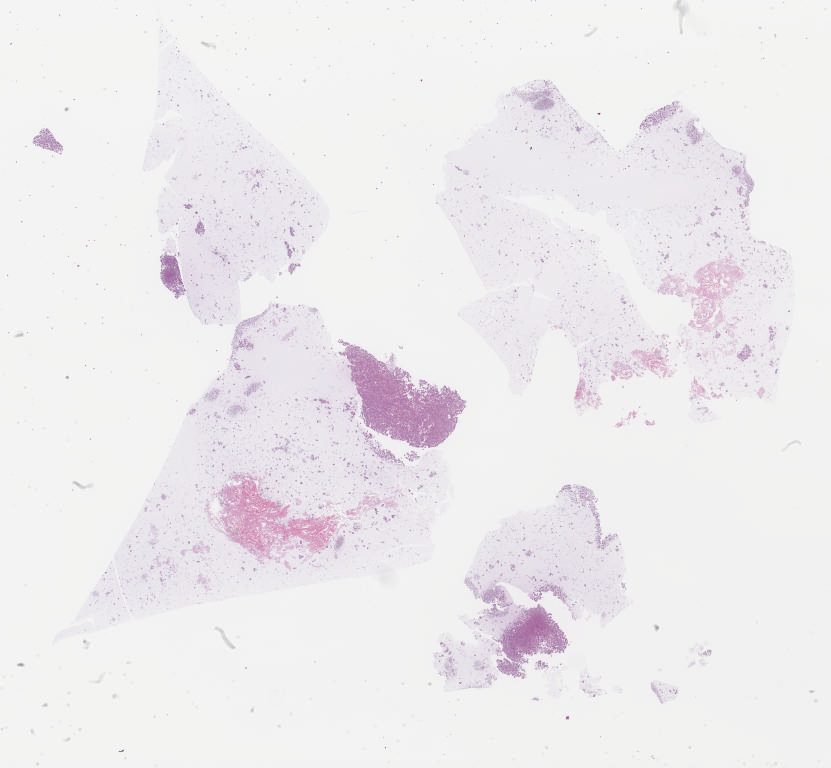

CellBlock.svs

96000

x

88641

@

40X